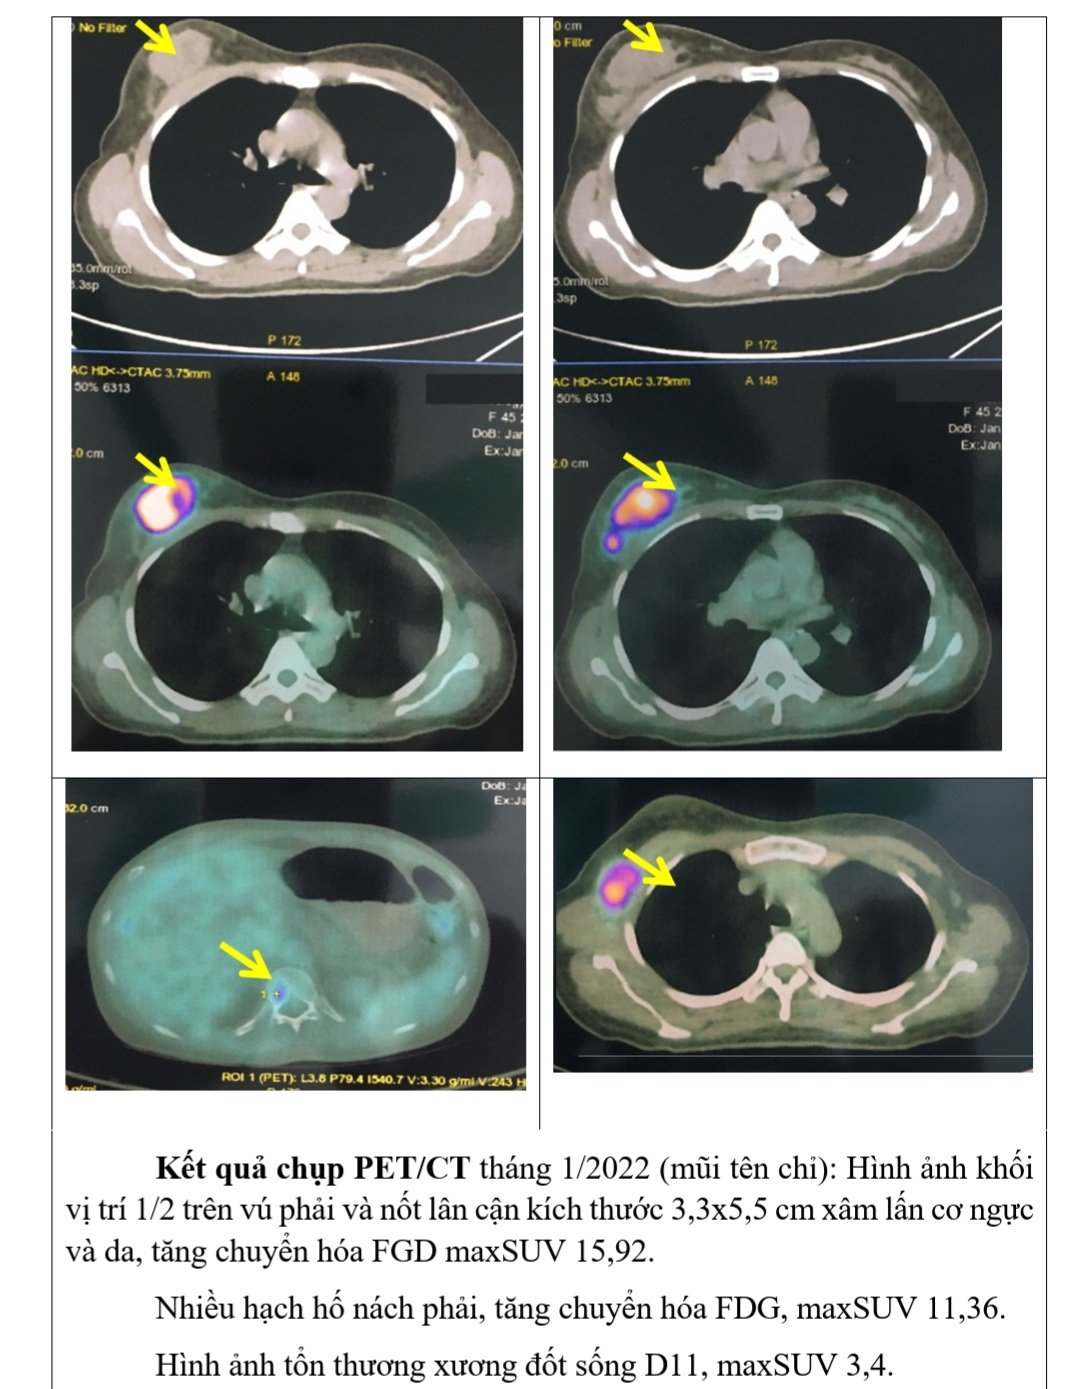

– Kết quả PET/CT: Hình ảnh khối vị trí 1/2 trên vú phải và nốt lân cận kích thước 3,3×5,5 cm xâm lấn cơ ngực và da, tăng chuyển hóa FGD maxSUV 15,92.

Nhiều hạch hố nách phải, tăng chuyển hóa FDG, maxSUV 11,36.

Hình ảnh tổn thương xương đốt sống D11, maxSUV 3,4.